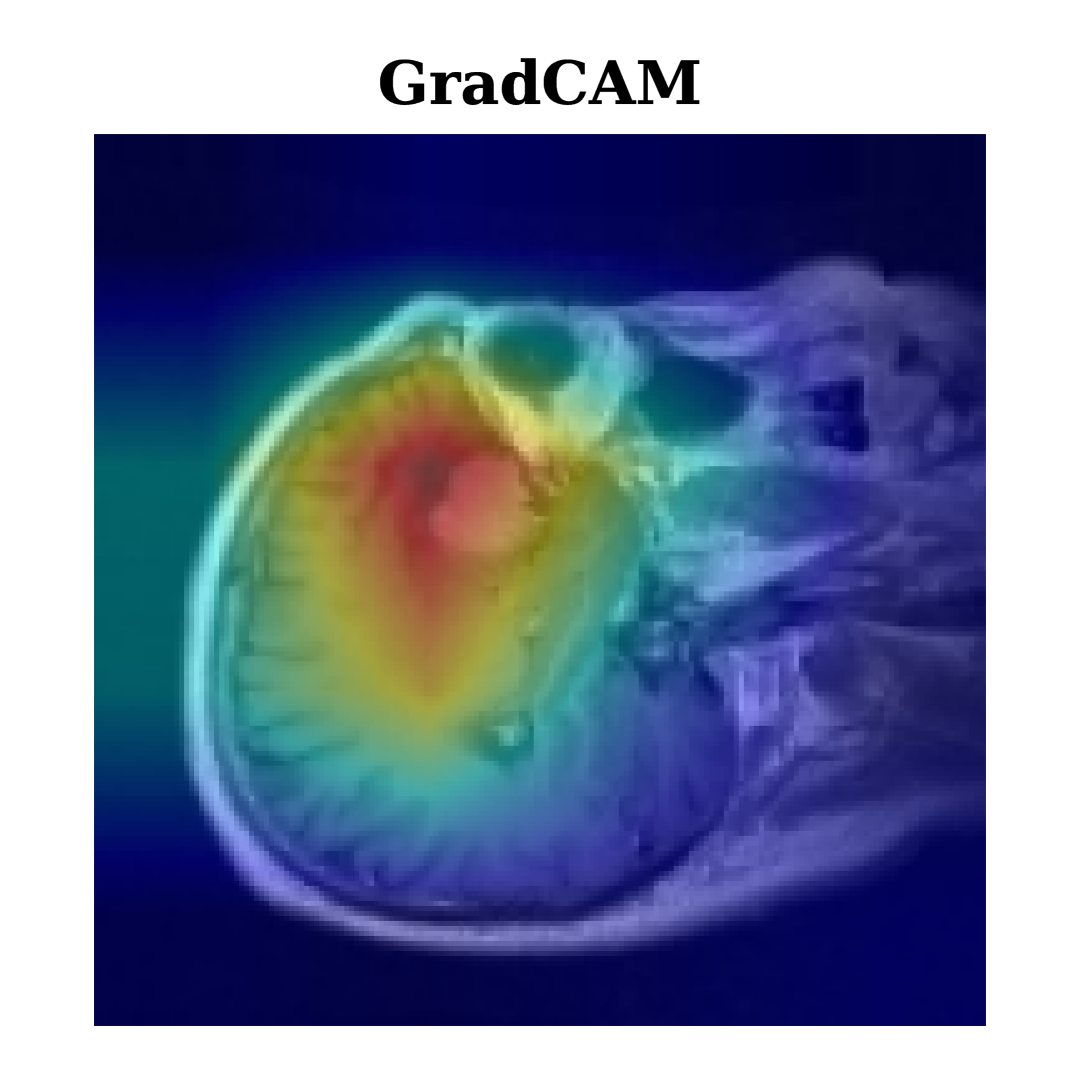

XAI includes techniques designed to enhance the transparency and interpretability of AI model decisions, hence making complex models more understandable to humans. Techniques like Grad-CAM and Grad-CAM++ highlight image areas that significantly influence a model’s output, helping users see which data aspects affect its predictions.

Grad-CAM and Grad-CAM++ are interpretability methodologies extensively employed in deep learning to visualize the critical areas of an input image that substantially influence a model’s classification result. Grad-CAM [16] functions by calculating the gradient of the class score YcY^{c} with respect to the feature maps AkA^{k}. The gradients are globally averaged to obtain significant weights αkc\alpha_{k}^{c} for each feature map AkA^{k}. The resultant weighted sum of the feature maps undergoes a ReLU activation to generate a heatmap that emphasizes the significant areas of the image. The equation for Grad-CAM [17] can be written as:

LGrad-CAMc=ReLU(kαkcAk)L_{\text{Grad-CAM}}^{c}=\text{ReLU}\left(\sum_{k}\alpha_{k}^{c}A^{k}\right)

By leveraging these higher-order gradients, Grad-CAM++ generates a more detailed and accurate heatmap, making it particularly effective for images with multiple objects or complex patterns, offering refined interpretability compared to Grad-CAM. Figure 5 demonstrates the utilization of Grad-CAM and Grad-CAM++ in our research, augmenting the interpretability of brain tumor classifications by offering critical insights into the decision-making processes of our deep learning models for tumor types including Menin, Glioma, and Tumor. Both techniques consistently capture similar critical regions, focusing on areas around the tumor’s core where distinguishing features are most prominent, thus supporting the reliability of model predictions across different tumor types.

Grad-CAM++ further refines these regions with more precise localization, particularly in complex cases like Glioma, where subtle boundaries exist between tumor and healthy tissue. This overlap in identified regions validates their importance for classification, with Grad-CAM++ offering a finer resolution that reveals deeper insights into tumor morphology. Comparing these XAI techniques provides a clearer understanding of feature importance by highlighting both similar and distinct regions, which strengthens interpretability and model transparency. This approach not only validates the model’s predictions but also enhances trust in AI as a precise and reliable tool in complex medical diagnostics, reinforcing its value in understanding tumor structures.